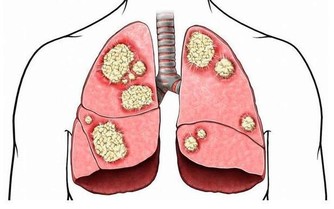

二、適量運動 運動對高血壓的重要性:有句話說:「年輕時,用健康換取金錢,年老時,用運動換取健康。」 運動除了可以促進血液循環,降低膽固醇的生成外,並能增強肌肉、骨骼與關節僵硬的發生。 運動能增加食慾,促進腸胃蠕動、預防便秘、改善睡眠。 有持續運動的習慣:最好是做到有氧運動,才會有幫助。 有氧運動同減肥一樣可以降低血壓,如散步、慢跑、太極拳、騎自行車和游泳都是有氧運動。 1、進行運動的注意事項: ①勿過量或太強太累,要採取循序漸進的方式來增加活動量。 ②注意周圍環境氣候:夏天:避免中午艷陽高照的時間;冬天:要注意保暖,防中風。 ③穿著舒適吸汗的衣服:選棉質衣料,運動鞋等是必要的。 ④選擇安全場所:如公園、學校,勿在巷道、馬路邊。 ⑤進行運動時,切勿空腹,以免發生低血糖,應在飯後2小時。 2、運動的禁忌 ①生病或不舒服時應停止運動 ②飢餓時或飯後一小時不宜做運動 ③運動中不可立即停止,要遵守運動程序的步驟 ④運動中有任何不適現象,應即停止 三、戒煙限酒 吸煙會導致高血壓。研究證明,吸一支煙後心率每分鐘增加5-20次/分,收縮壓增加10-25mmhg。這是為什麼呢? 因為煙葉內含有尼古丁(煙鹼)會興奮中樞神經和交感神經,使心率加快,同時也促使腎上腺釋放大量兒茶酚胺,使小動脈收縮,導致血壓升高。尼古丁還會刺激血管內的化學感受器,反射性地引起血壓升高。 長期大量吸煙還會促進大動脈粥樣硬化,小動脈內膜逐漸增厚,使整個血管逐漸硬化。 同時由於吸煙者血液中一氧化碳血紅蛋白含量增多,從而降低了血液的含氧量,使動脈內膜缺氧,動脈壁內脂的含氧量增加,加速了動脈粥樣硬化的形成。 因此,無高血壓的人戒煙可預防了高血壓的發生,有高血壓的人更應戒煙。 與吸煙相比,飲酒對身體的利弊就存在爭議。 不時出現各種報告,有的說飲少量酒有益,有的說有害,但可以肯定的一點是,大量飲酒肯定有害,高濃度的酒精會導致動脈硬化,加重高血壓。 四、心理平衡 高血壓患者的心理表現是緊張、易怒、情緒不穩,這些又都是使血壓升高的誘因。 患者可通過改變自己的行為方式,培養對自然環境和社會的良好適應能力,避免情緒激動及過度緊張、焦慮,遇事要冷靜、沉著; 當有較大的精神壓力時應設法釋放,向朋友、親人傾吐或鼓勵參加輕鬆愉快的業餘活動,將精神傾注於音樂或寄情於花卉之中,使自己生活在最佳境界中,從而維持穩定的血壓。 五、自我管理 1、定期測量血壓,1-2周應至少測量一次。 2、治療高血壓應堅持「三心」,即信心、決心、恆心,只有這樣做才能防止或推遲機體重要臟器受到損害。 3、定時服用降壓藥,自己不隨意減量或停藥,可在醫生指導下及現病情加予調整,防止血壓反跳。 4、條件允許,可自備血壓計及學會自測血壓。 5、隨服用適當的藥物外,還要注意勞逸結合、注意飲食、適當運動、保持情緒穩定、睡眠充足。 6、老年人降壓不能操之過急,血壓宜控制在140-159mmhg為宜,減少心腦血管併發症的發生。 7、老年人及服用去甲腎上腺素能神經末梢阻斷藥的防止體位性低血壓。 8、不需要嚴格禁止性生活:注意以下幾種情況,不宜進行性生活; ①事後不要立即進行房事; ②酒後應禁止性生活; ③若有頭暈,胸悶等不適應停止性生活,並及時就醫。